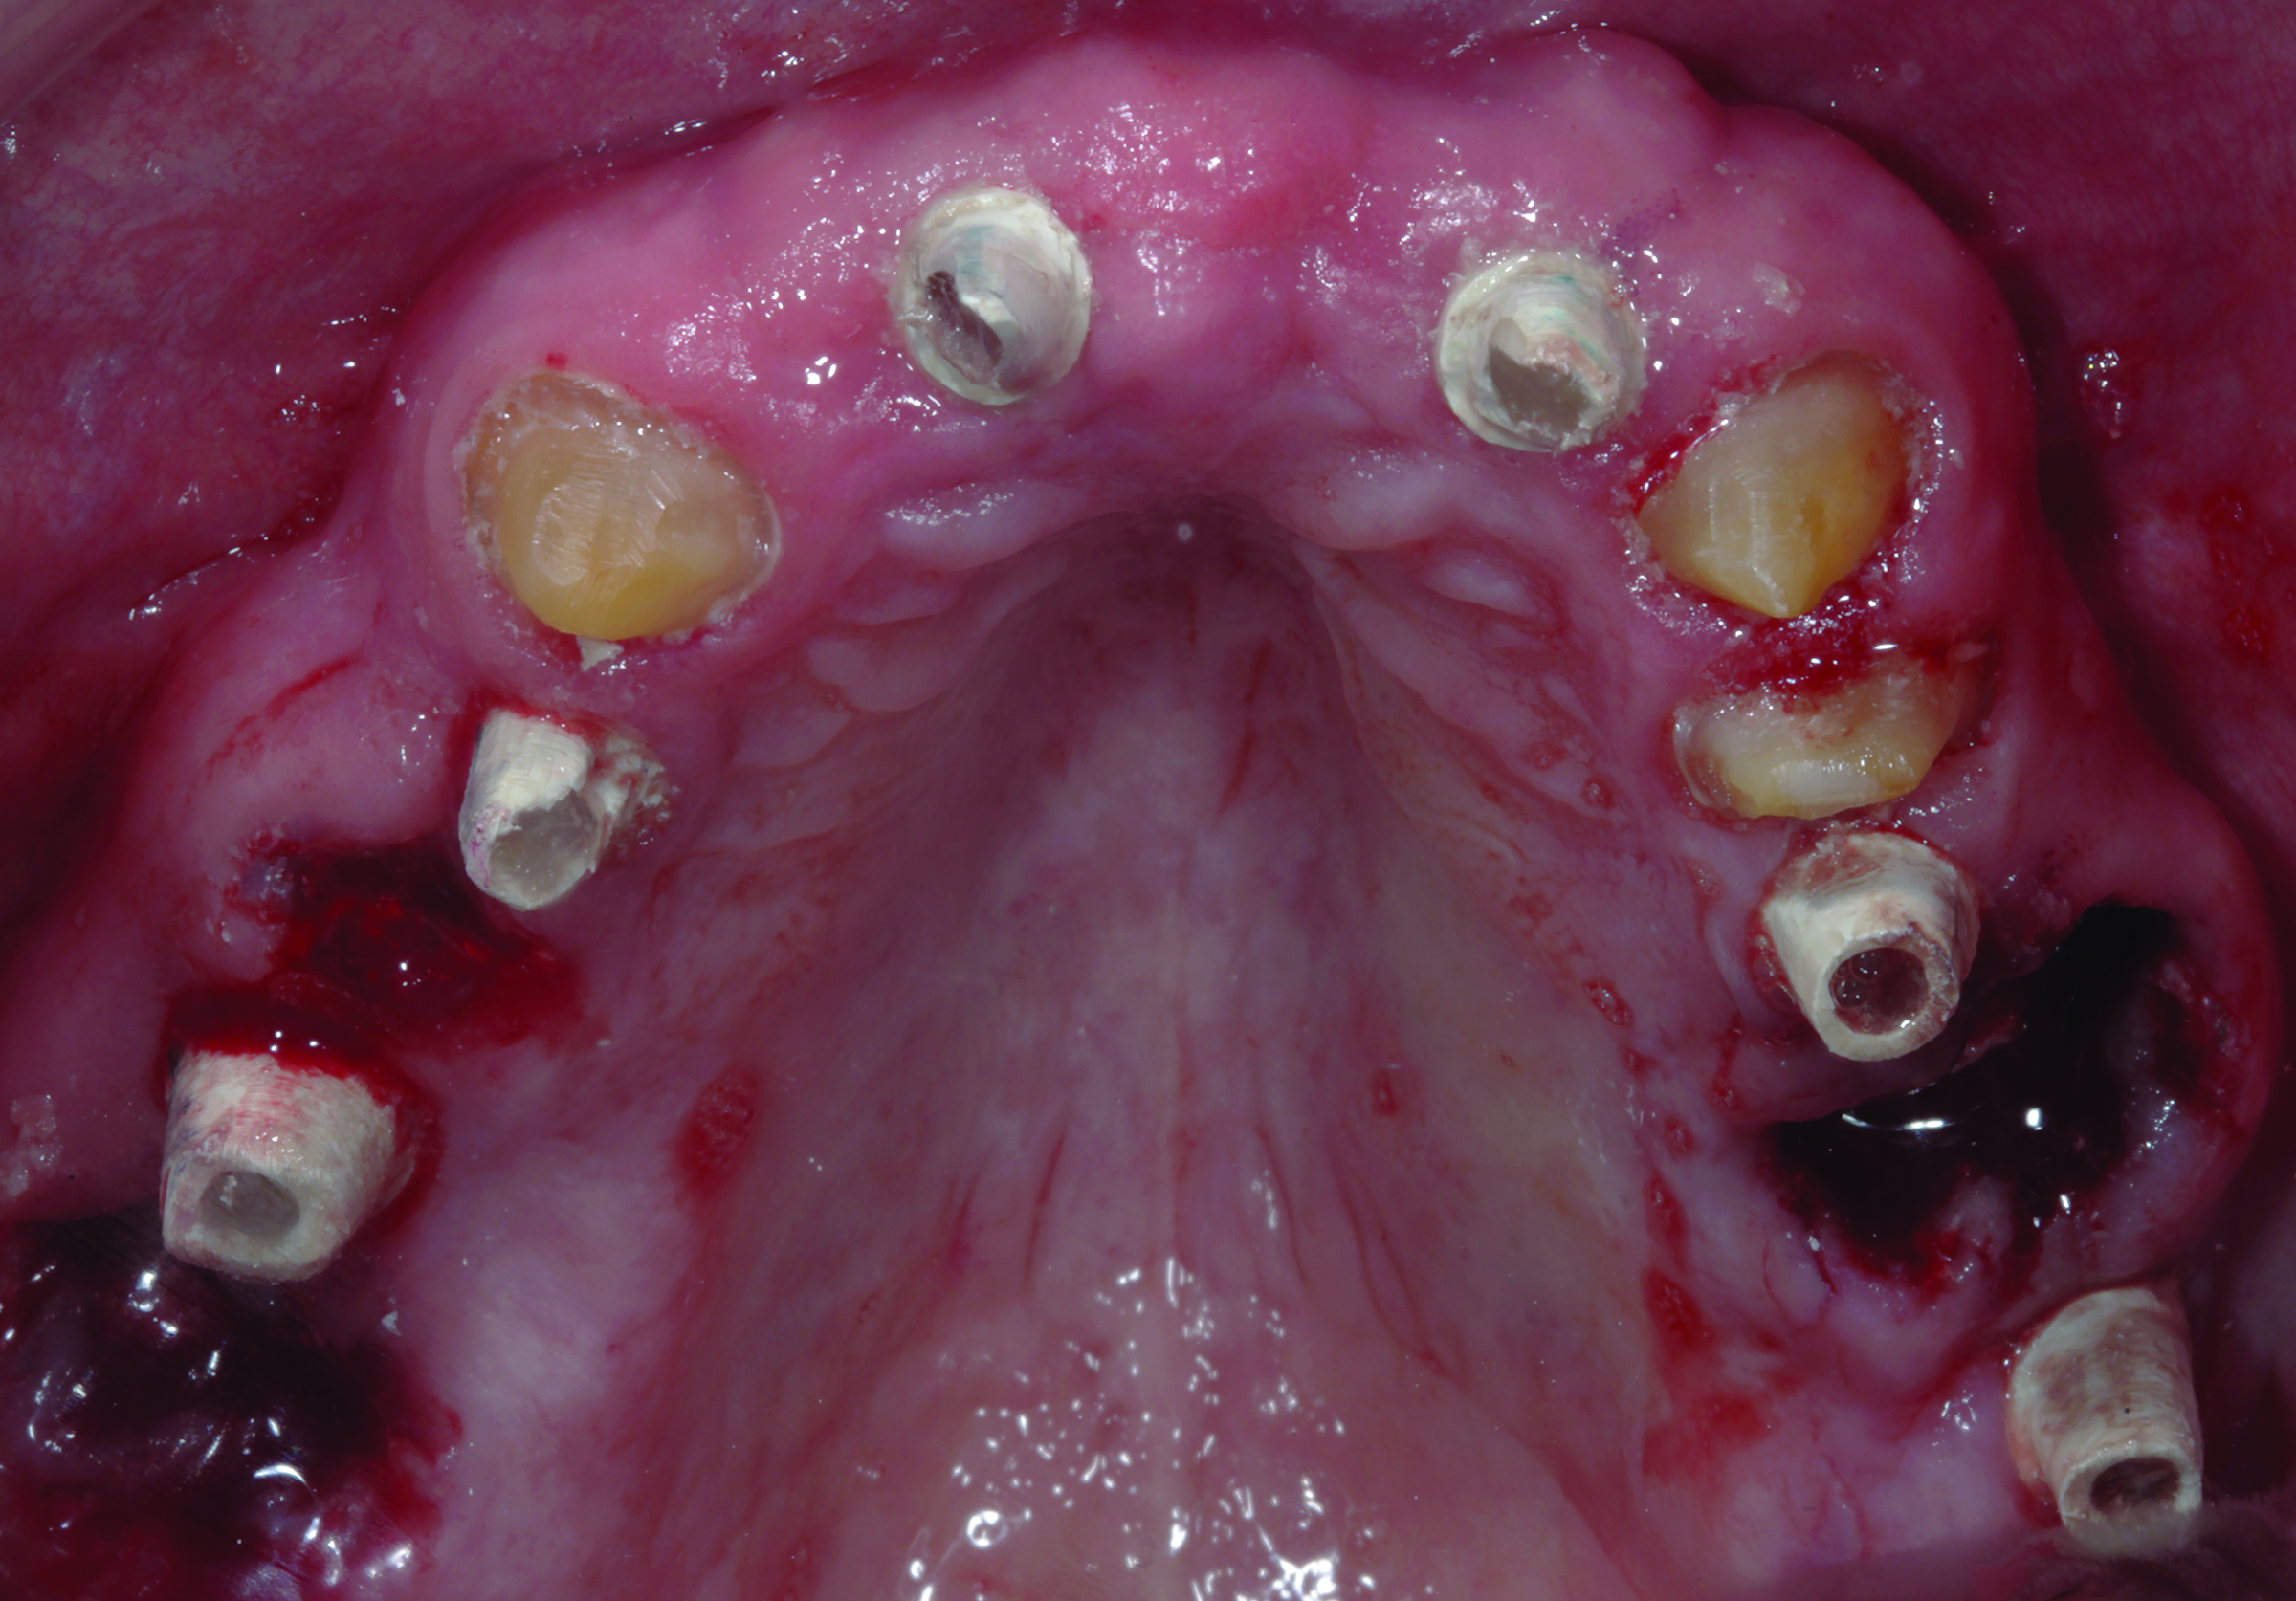

Fig 3. The try-in of the laboratory-processed PMMA shell has the abutments in place prior to connecting and pickup. A portion of a palate acts as a stop for acrylic resin support.

Figure 3

Fig 4. Before final impression making, the ovate pontic receptor sites and emergence profiles can be seen. They are created with the aid of the provisional prosthesis.

4

Figure 4